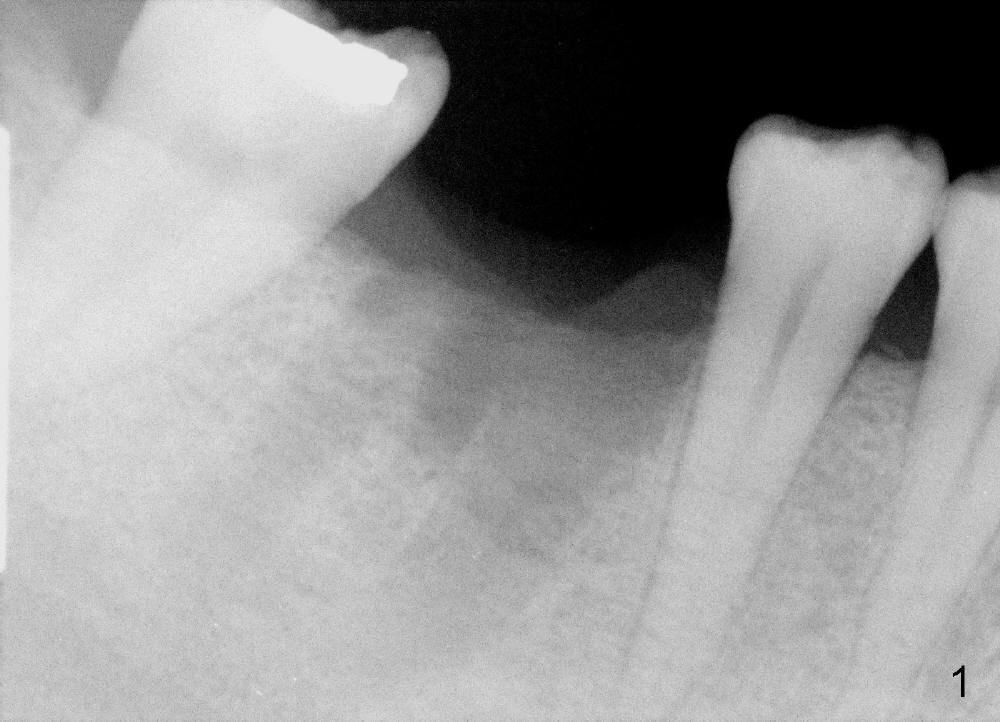

A 43-year-old lady had the lower right first molar extracted in other office last month. The socket appears to be healing normally (Fig.1). Tatum tapered implant 6x17 mm is planned (Fig.2). The implant is to be placed inside the septum (Fig.3 red outline; black: mesial and distal sockets; yellow: the upper border of the inferior alveolar canal). Either 1.5 mm pilot drill or 2 mm RT is used to start osteotomy in the septum at the depth of 17 mm (Fig.4 white outline). The osteotomy is enlarged with alternating use of osteotomes and 17 mm series tapered drills or Bicon reamers if autogenous bone will be needed (Fig.5 black), while the septal bone is pushed mesiodistally (arrows). After application of taps, an appropriately sized implant is placed (Fig.6 white). The septal bone continues expanding (arrows), whereas the mesial and distal sockets are being decreased.